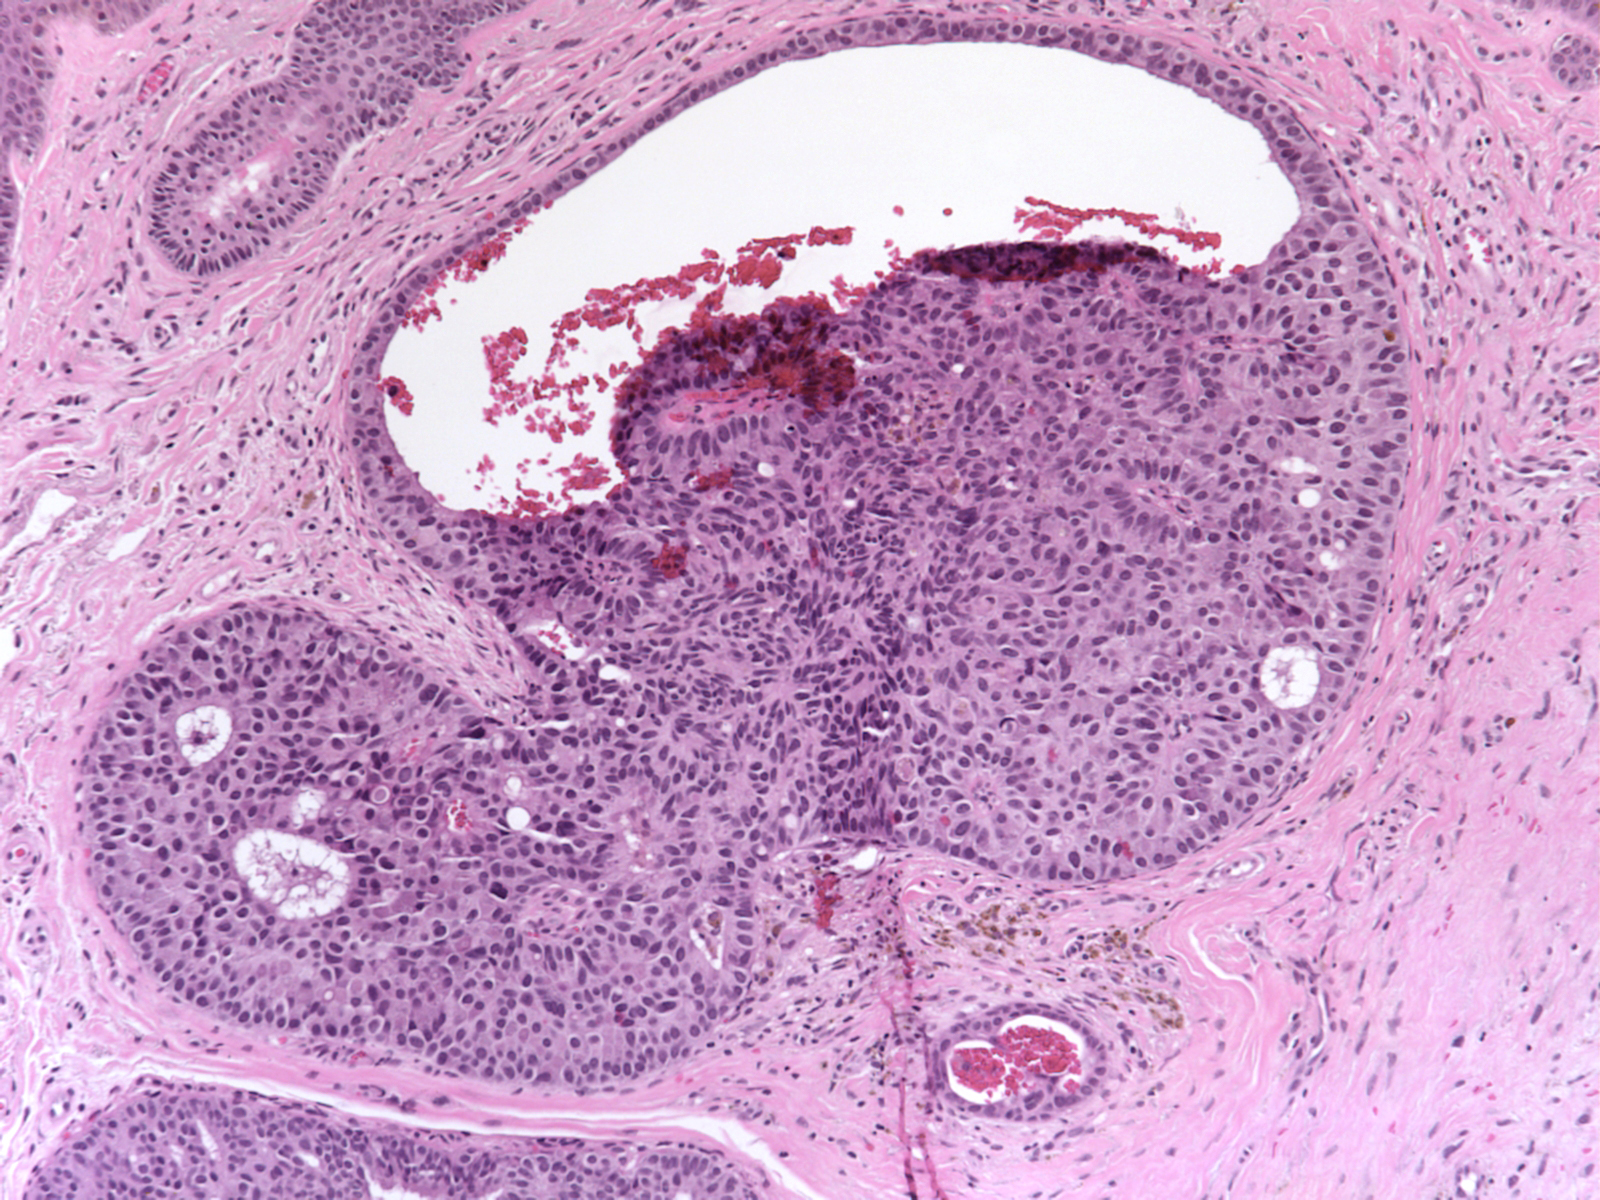

(A) Tubular pattern of basal cell neoplasm showing wellformed tubules Glandular Neoplasm Glandular cells on a pap test are usually cells from the. These glands secrete mucus and digestive juices. Most breast, colon, esophageal, pancreatic, and prostate cancers are adenocarcinomas. glandular abnormalities are also associated with a substantial risk of cervical intraepithelial neoplasia grade 3 (cin3) and cervical. adenocarcinoma is a type of cancer that affects glands and glandular tissues.. Glandular Neoplasm.